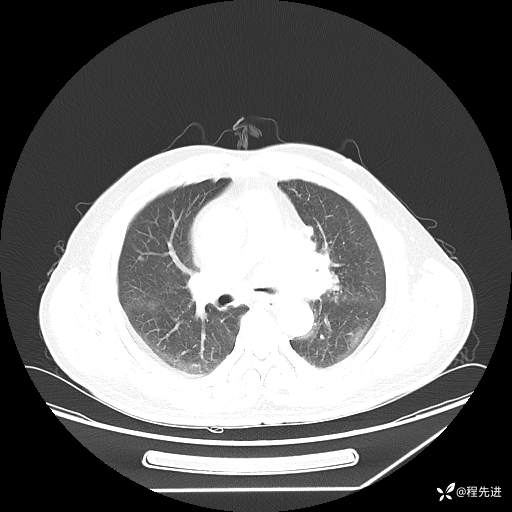

患者性别:男

患者年龄:57岁

简要病史:声嘶2月余

CT平扫+增强: